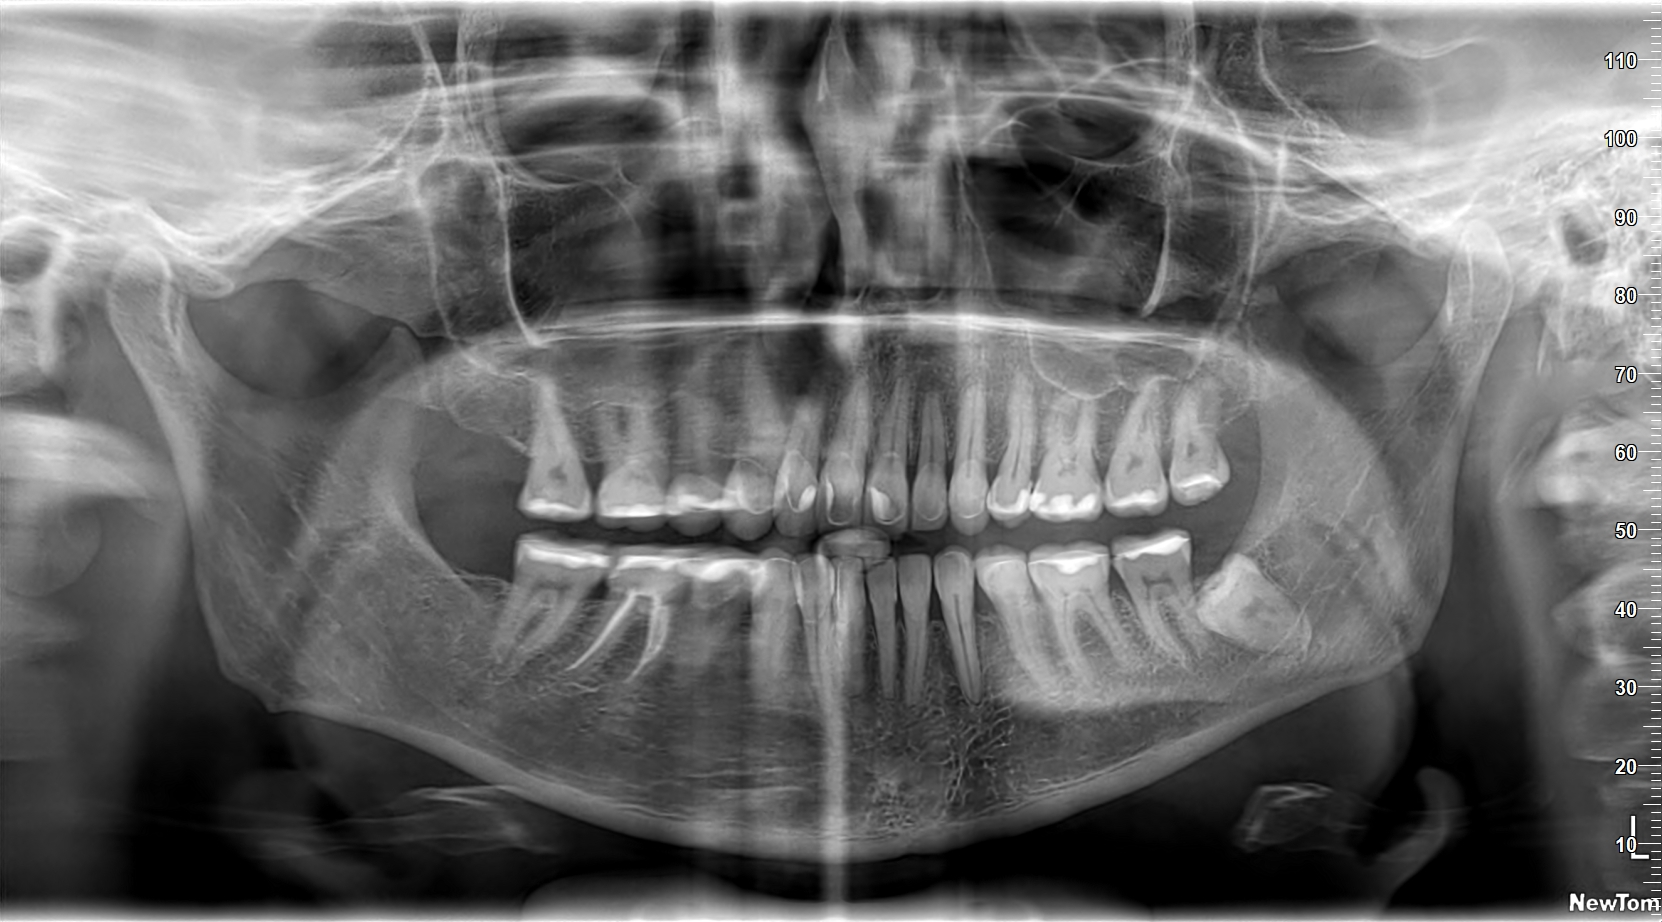

Welcome package 2 Consultație și plan de tratament Test Drive Your Smile Igienizare dentară completă Tomografia computerizată CBCT